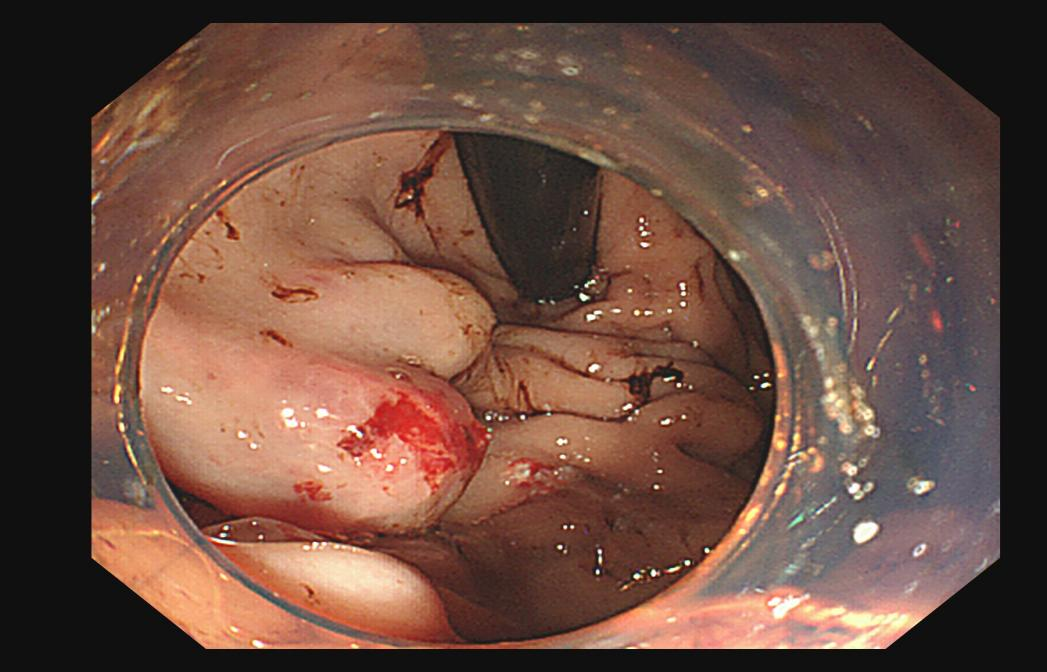

镜下直击:胃底的“致命暗流”

在麻醉医生的护航下,胃镜轻柔而迅速地经口进入。镜头掠过食管,当视野进入胃底时,所有医护人员的心都揪紧了——只见多条粗大、迂曲的蓝色静脉像怒张的蚯蚓盘踞在胃底黏膜下,其中一处曲张静脉表面可见破口,正有暗红色的血液飚出。诊断明确:胃底静脉曲张破裂出血。

这正是导致女孩严重贫血、输血难以纠正的“元凶”。这种出血往往量大事急,如同决堤暗流,传统药物保守治疗难以奏效。